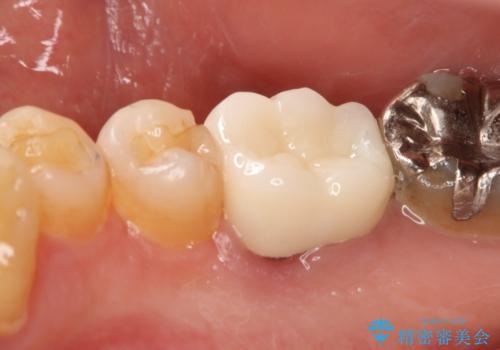

- 保険で治療された右下5番をセラミックにやり変え希望の患者様です。

切削量などを考慮し、セラミックインレーでの治療を選択しました。

古い材料と虫歯を全て除去した上で形成・印象を行い、セラミックインレーを装着しています。